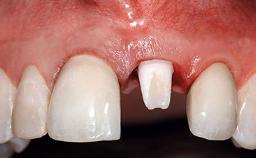

A 15-year-old male patient was referred to us by his pediatric dentist in June 2004 for evaluation of treatment options for his failing tooth 21. The patient had recently seen an endodontist for internal bleaching and been advised that there had been significant resorption and ankylosis. The patient’s mother was concerned because the tooth appeared shorter than the adjacent one. His past dental history was significant for trauma (September 2001), where the tooth had been avulsed and reimplanted. Teeth 11 and 21 had been endodontically treated.